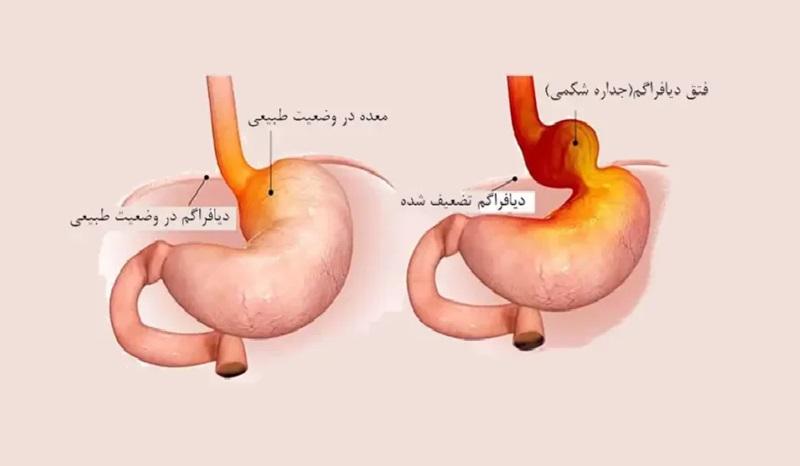

فتق دیافراگم زمانی رخ میدهد که بخشی از معده یا سایر اعضای شکمی از طریق شکافی در دیافراگم (عضله جداکننده قفسه سینه و شکم) به درون قفسه سینه نفوذ میکنند. این وضعیت میتواند مادرزادی باشد یا در طول زندگی ایجاد شود.